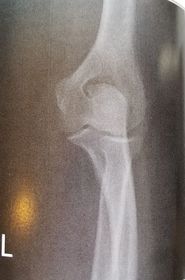

| AP Elbow | humerus is externally rotated because the epicondyles are not in profile |

| AP Oblique Elbow Internal Rotation | Insufficient obliquity |

| AP Oblique Elbow Internal Rotation | Excessive obliquity |

| AP Oblique Elbow External Rotation | forearm is not parallel to IR capitulum-radial joint is closed olecranon is not in the fossa |

| AP Oblique Elbow External Rotation | Underrotation distal forearm slightly elevated |

| AP Oblique Elbow External Rotation | Overrotation |

| Lateral Elbow | The elbow is elevated above the level of the shoulder radial head anterior to coronoid - should be superimposed capitulum too proximal to trochlea radial tuberosity seen - hand is pronated |

| Lateral Elbow | Elbow is depressed below the level of the shoulder radial head superimposed by coronoid capitulum too distal to medial trochlea |

| Lateral Elbow | the distal wrist is elevated hand is pronated because you can see the radial tuberosity - should not see that |

| AP Elbow | ANATOMY: distal humerus - proximal forearm CRITERIA: slight superimposition of proximal radius/ulna humeral epicondyles in profile open joint space POSITIONING: CR perpendicular @ midelbow |

| Medial Oblique Elbow | ANATOMY: proximal radius/ulna, distal humerus, medial epicondyle and trochlea CRITERIA: coronoid process in profile radial head and neck should superimpose the ulna olecranon process seen within olecranon fossa POSITIONING: CR perpendicular @ midelbow |

| Lateral Oblique Elbow | ANATOMY: open joint space, radial head, neck, tuberosity, and capitulum CRITERIA: radial head, neck, and tuberosity are free of superimposition humeral epicondyles and capitulum in profile POSITIONING: CR perpendicular @ midelbow |

| Lateral Elbow Evaluation Criteria | ANATOMY: distal humerus, proximal forearm, entire elbow joint CRITERIA: humeral epicondyles are superimposed radial tuberosity is invisible (if visible the hand is pronated) half of the radial head superimposed by coronoid process Elbow is flexed 90 degrees to see/not see fad pads 3 concentric arcs visible POSITIONING: CR perpendicular @ lateral epicondyle |